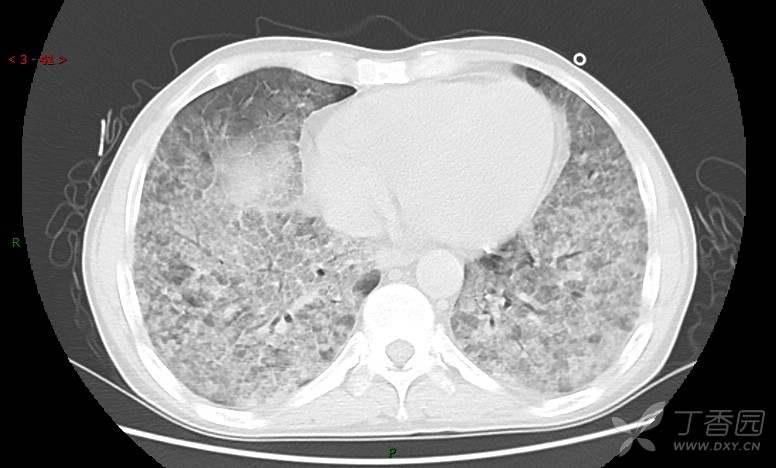

地图+铺路石征=PAP?那升高的CEA怎么说(病例3连发,附其他2例链接)

原帖名:刚入手的病例,看着都憋得慌,有PET/CT,请讨论(病例3连发,附其他2例链接)

患者男,42岁,咳嗽半年余,加重伴憋喘2月余。

患者半年余前无明显诱因出现间断咳嗽,干咳为主,偶咳少量黄白痰,剧烈咳嗽或运动后可出现轻度憋喘,无高热、脓臭痰,无胸痛、咯血及晕厥,无低热乏力及盗汗,无心前区压榨感及夜间阵发性呼吸困难,初未在意,未予正规诊治。2月余前患者自觉上述症状较前加重,咳嗽、憋喘明显,黄白色粘痰略有增多,伴有发热,热前伴有畏寒、寒战,体温最高达38.9℃,先后就诊多家医院,入住重症监护室,未行气管插管,考虑“重症肺炎”,给予“美罗培南、复方磺胺甲噁唑”等药物抗感染,“卡泊芬净”抗真菌,并给予“甲泼尼龙”等药物治疗35天,经治疗后症状好转于2018-04-02出院。患者自出院后仅应用中药治疗(具体不详),并给予家庭氧疗,平素仍有间断咳嗽,咳少量黄白色粘痰,活动后憋喘明显,活动耐量差,以卧床为主。

肺内弥漫性网状结节影,PET-CT却无阳性病灶,这是?(附其他2例链接)